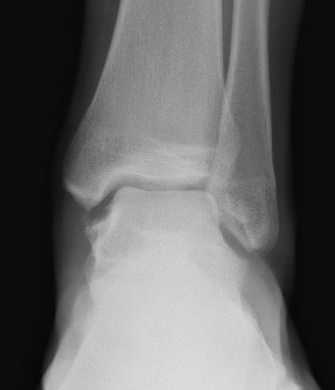

Xray

Syndesmotic injury with high grade deltoid injury

Ankle dislocation with soft tissue injury to Deltoid and syndesmsosis

Ankle fractures with deltoid ligament rupture / Bimalleolar equivalent injury

Maisonneuve injury with proximal fibular fracture and increased medial clear space

Weber B with increased medial clear space on CT

Weber C with increased medial clear space